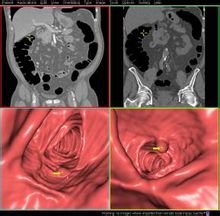

肿瘤